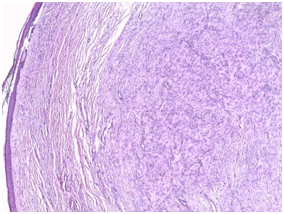

The patient underwent surgical excision. Histological examination showed a subatrophic polypoid epidermal coating with fusiform cells arranged in wavy bays. They are provided with regular elongate ovoid nuclei arranged in places in blanks of palisades with rolls of nodules in places (Figure 2).The patient benefited from an excision with good evolution without recurrence after one year.

Figure 2 Histological images showing a proliferation of fusiform fused cells with pissed nuclear disposition and some coils.